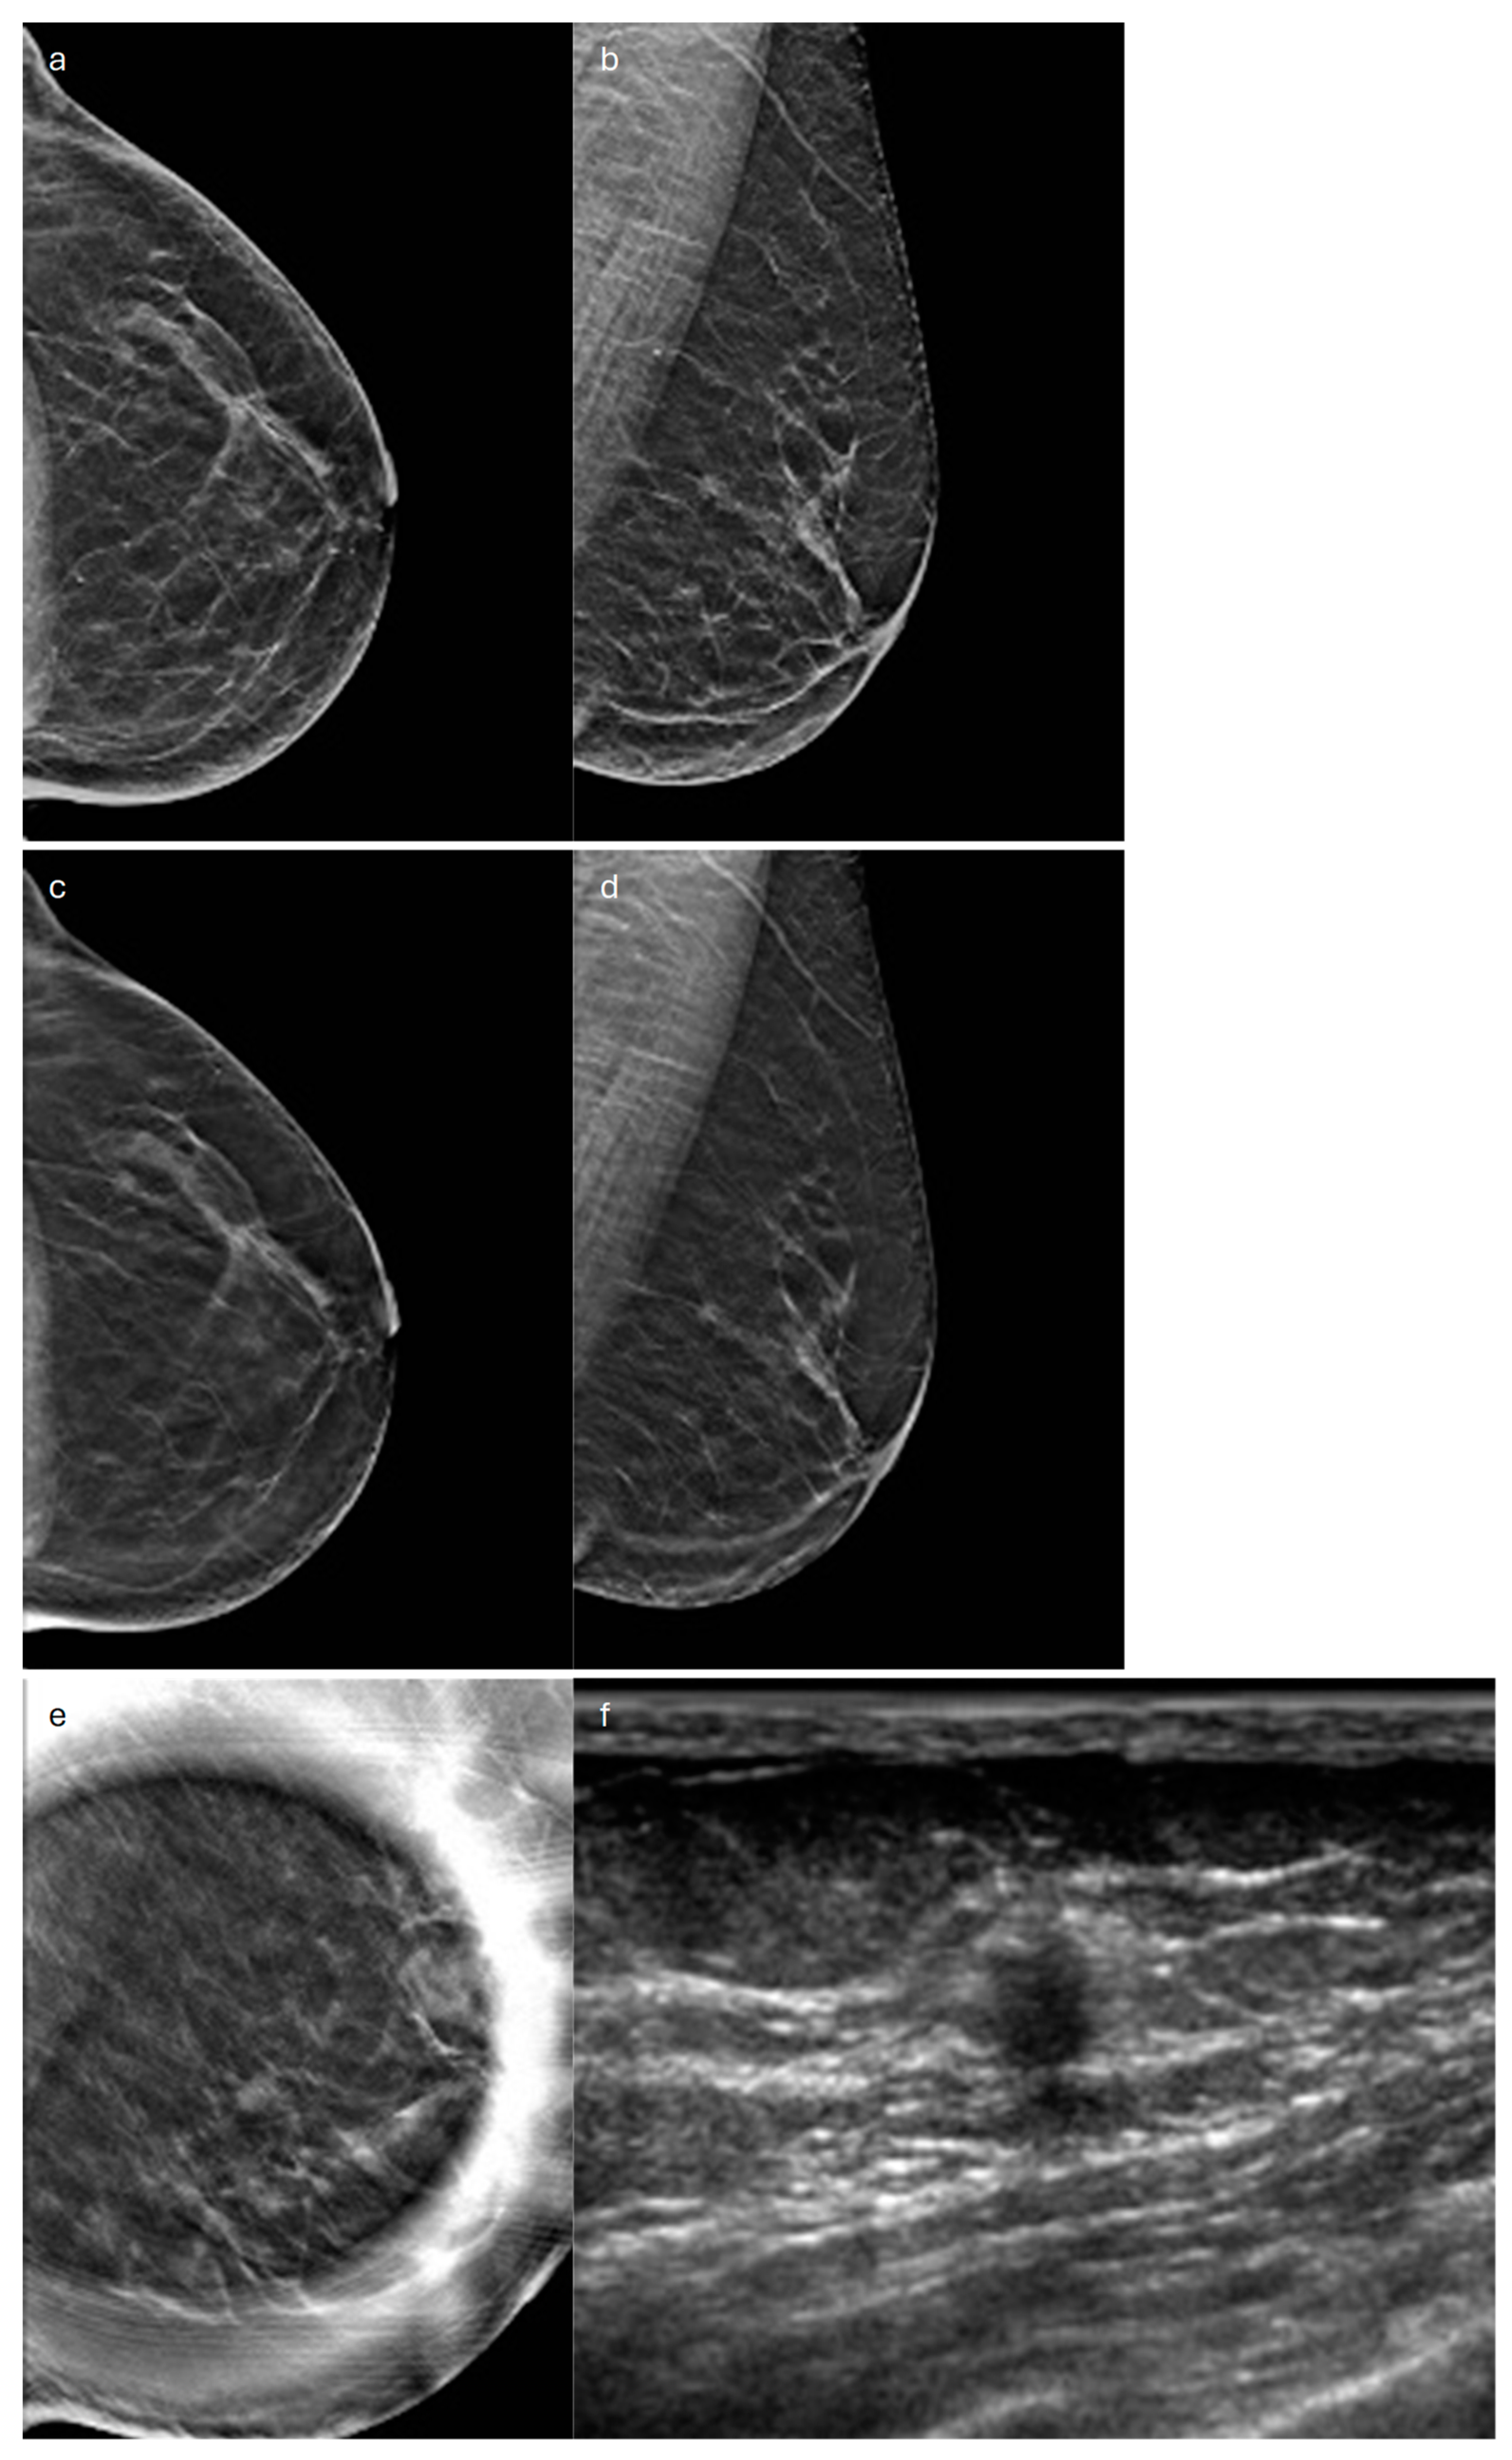

3. Tubular